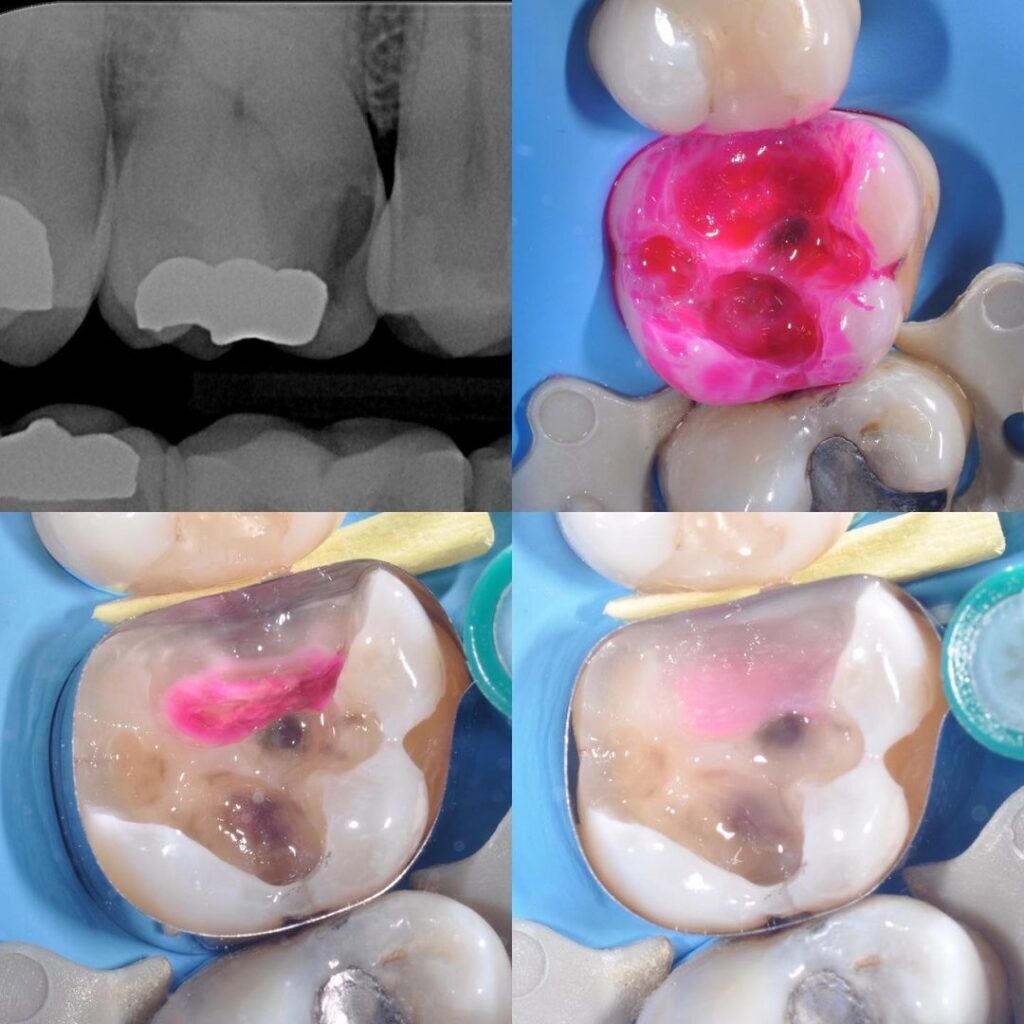

Chairside materials - caries detector, teethmate™ f-1 2.0